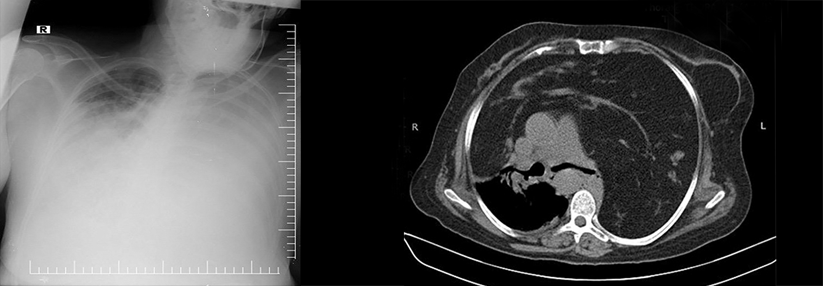

Bei der Frage, ob ein bestimmter Patient in die Klinik muss oder nicht, gibt bereits der HEART-Score dem Rettungsdienst wichtige Hinweise. Bei der Frage, ob ein bestimmter Patient in die Klinik muss oder nicht, gibt bereits der HEART-Score dem Rettungsdienst wichtige Hinweise. © iStock/turk_stock_photographer